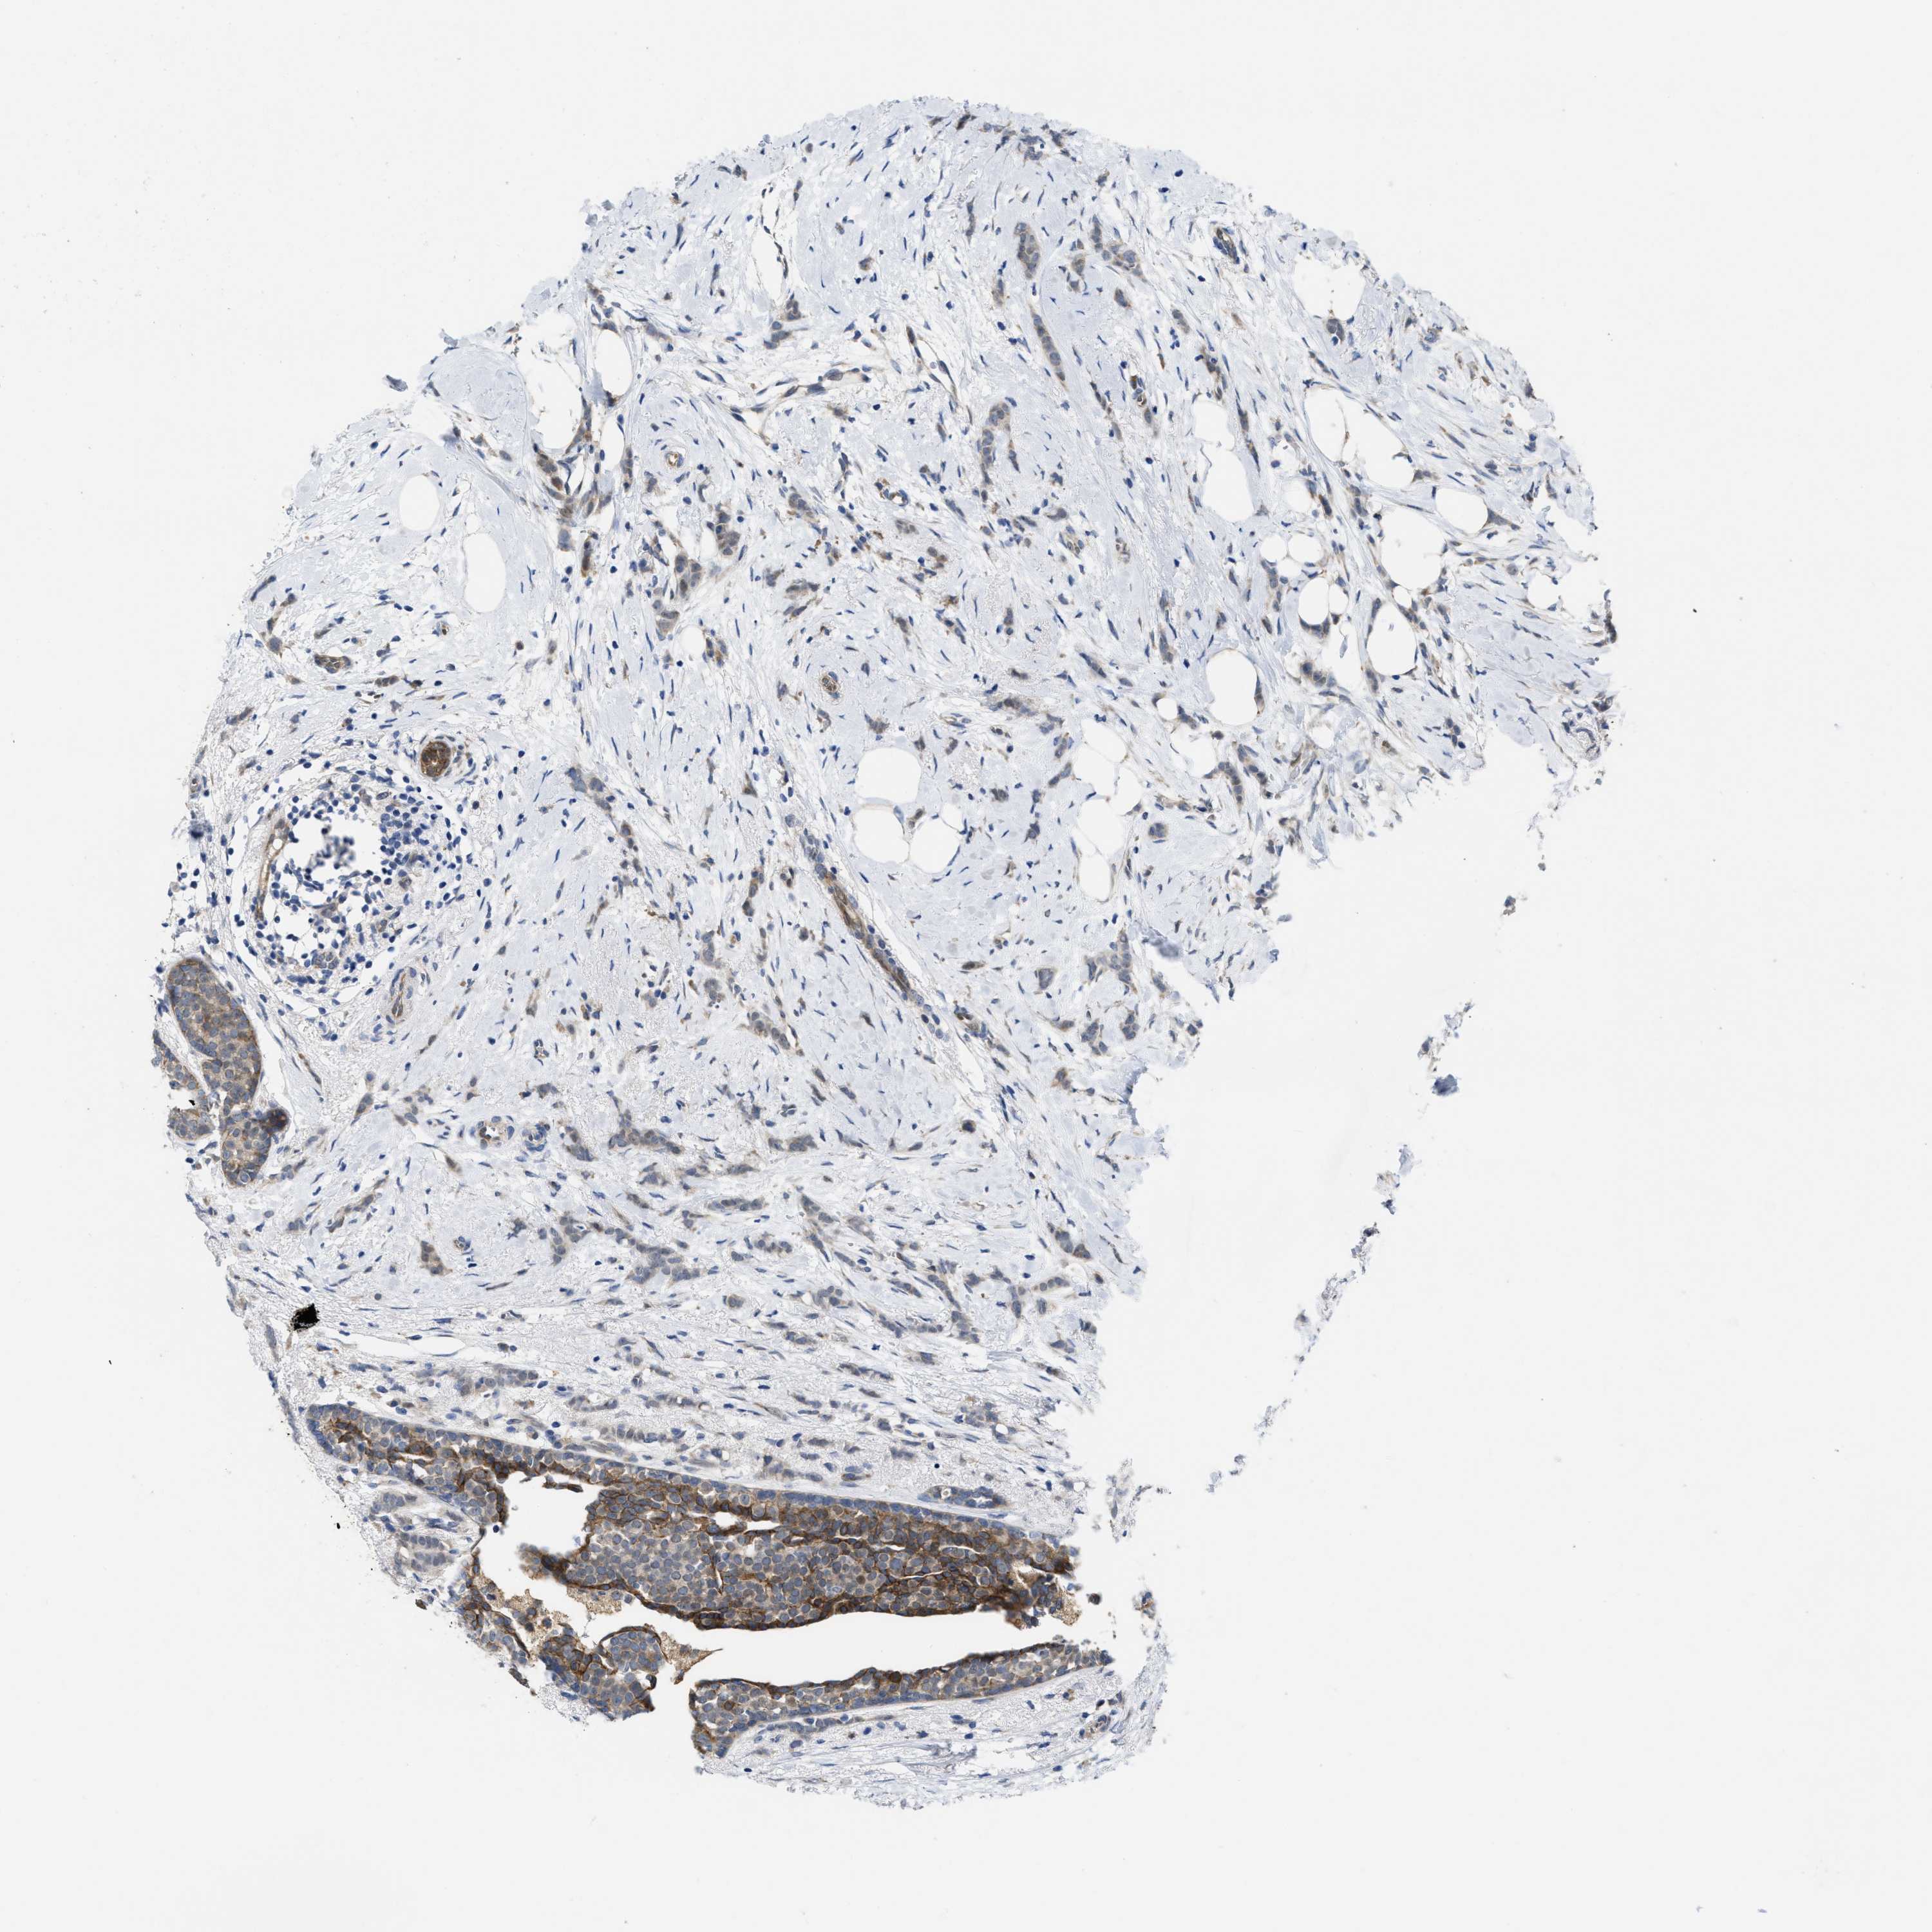

CANCER BREAST CANCER Show tissue menu

BRCA TCGA BRCA VALIDATION PROTEIN EXPRESSION

Breast cancer

Human cancer

Breast invasive carcinoma